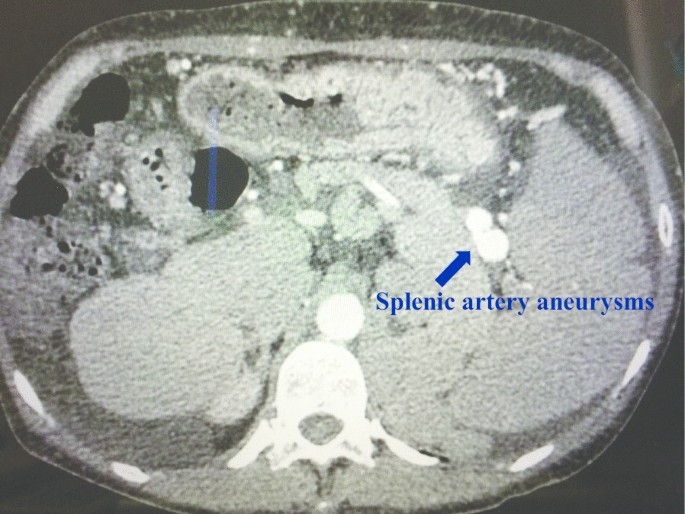

A 51-year-old female patient was admitted to explore the possibility of liver transplantation for liver failure due to IPH. She had NRH on liver biopsy 20 years ago and was diagnosed with IPH. The patient’s extrahepatic portal vein showed a scar-like stenosis, and the portal flow was completely hepatofugal. Collateral circulation such as the splenorenal shunt was well developed, and dense calcification was observed at the site of splenomesenteric junction (Fig. 1), suggesting that the usual portal reconstruction would be impossible. Furthermore, multiple splenic artery aneurysms (SAAs) up to 2 cm were observed in the splenic hilum (Fig. 2). The patient’s condition was getting worse and her Child–Pugh score became 13, and her Model for End-Stage Liver Disease (MELD) score increased to over 40 because of renal dysfunction, requiring temporary dialysis. Due to the high risk of rupture during the perioperative period of liver transplantation, it was considered necessary to take some preventive measures against the SAAs; however, it was difficult to perform preoperatively due to her medical condition. Therefore, splenectomy at the time of transplantation was needed. Since the splenorenal shunt was likely to be destroyed during splenectomy, portal vein reconstruction using renoportal anastomosis was considered to not be possible. For the jumping vein graft, long-term patency was a concern because it passed through a non-physiological route. We decided to use an interposition autologous graft between the splenomesenteric junction and the graft portal vein stump.

Splenic artery aneurysms (SAAs), occurring in 7% to 17% of patients with cirrhosis, often result in catastrophic rupture after liver transplantation [11]. SAAs are closely related to severe portal hypertension with large portosystemic collaterals. While visceral aneurysms larger than 2 cm are more likely to rupture, preventive treatment should be encouraged regardless of the size of SAAs, because the risk of rupture increases during the perioperative period of liver transplantation, in which hemodynamic and proteolytic changes occur [11, 12]. Whether to select interventional radiology (IVR) or surgical treatment such as splenectomy as a treatment method needs to be individually selected according to the patient’s general condition, and the location and number of SAAs.